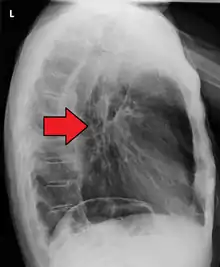

Although an occlusive tumor may be suspected on a barium swallow or barium meal, the diagnosis is best made with an examination using an endoscope. This involves the passing of a flexible tube with a light and camera down the esophagus and examining the wall, and is called an esophagogastroduodenoscopy. Biopsies taken of suspicious lesions are then examined histologically for signs of malignancy.

Additional testing is needed to assess how much the cancer has spread (see § Staging, below). Computed tomography (CT) of the chest, abdomen and pelvis can evaluate whether the cancer has spread to adjacent tissues or distant organs (especially liver and lymph nodes). The sensitivity of a CT scan is limited by its ability to detect masses (e.g. enlarged lymph nodes or involved organs) generally larger than 1 cm.[43][44] Positron emission tomography is also used to estimate the extent of the disease and is regarded as more precise than CT alone.[45] PET/MR as a novel modality has shown promising results in preoperative staging with fair feasibility and good correlation in comparison to PET/CT. It can enhance tissue differentiation with lowering the radiation dose to the patient.[46] Esophageal endoscopic ultrasound can provide staging information regarding the level of tumor invasion, and possible spread to regional lymph nodes.

Contrast CT scan showing an esophageal tumor (axial view)

Contrast CT scan showing an esophageal tumor (coronal view)